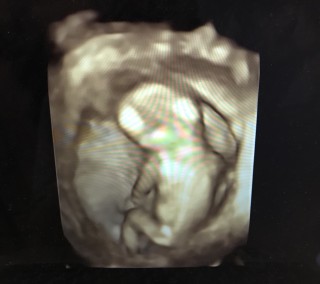

初めての4Dエコーに感動!可愛いく撮ってもらえました!8.1センチ!4週に1度の検診になり無事に育ってるか不安だったのでとっても嬉しかったです!

手を膝に付いて、何かを考えているようなポーズです。4Dに切り替えるとなぜか後ろ向きの姿しか見せてくれず…笑前回よりも一段と人間らしくなっている様子を見ることができ、感動しました!次の4週間後の検査は、赤ちゃんのお股を見てみましょうと言われました(^^)

初4D☆ 残念ながらお顔は見せてくれませんでしたが、足を曲げ伸ばししているところは見られました。 手足が長くてスタイル良さそうw もしかしたら男の子かな~とのことです。

4週間ぶりの検診! 今日から腹部エコー(*^^*) 4Dはリアルでしたが お腹の中をバシバシ叩いて 仰け反って暴れていました(笑) 足を組んで偉そうに 寝ていました(笑) 誰に似たんだかと言ったら 旦那にちらっと見られましたが この調子で全て順調に いくことを願うばかりです(´・_・`)